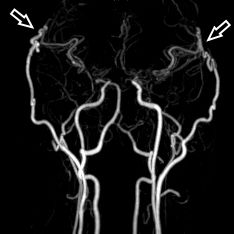

Angiographie beidseitige Moyamoya Krankheit

Konventionelle Angiographie eines Patienten mit beidseitiger Moyamoya Krankheit (links). 3-dimensionale Darstellung eines Aneurysmas einer jahrelang stark beanspruchten Spontan-Kollaterale (rechts).